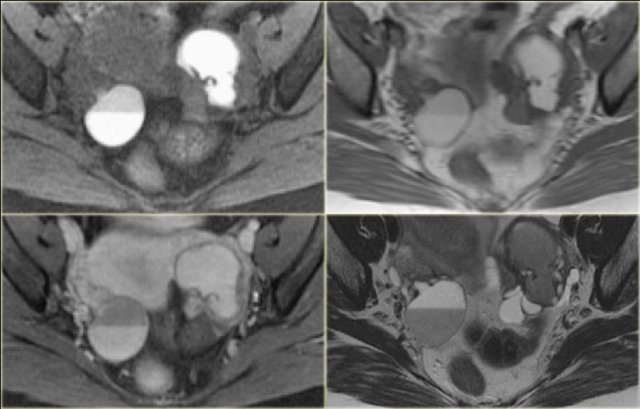

On ultrasound both ovaries are markedly enlarged and contain cystic components with intracystic solid components (arrows).

The complex solid-cystic lesions, in addition to being bilateral, are suspicious for a cystic ovarian neoplasm and warrant further evaluation.

CT of the same patient confirms large bilateral complex solid-cystic lesions, bulging into the abdomen.

The purpose of the CT is not to confirm what was already known from the ultrasound, but to stage disease.

On the basis of CT (or of MRI) it is not possible to determine the histologic type of the tumor.

This is not relevant. This patient will undergo surgery.

For epithelial tumors - by far the most common group of malignant ovarian tumors - even after surgery, the exact tumor subtype is much less important for the prognosis than factors such as FIGO-stage, tumor differentation grade, and how succesful surgery was in removing all of the disease.

For this patient the relevant findings are on the image on the left.

There is a peritoneal implant.

The tumor was resected and pathology showed this was an endometrioid ovarian carcinoma.